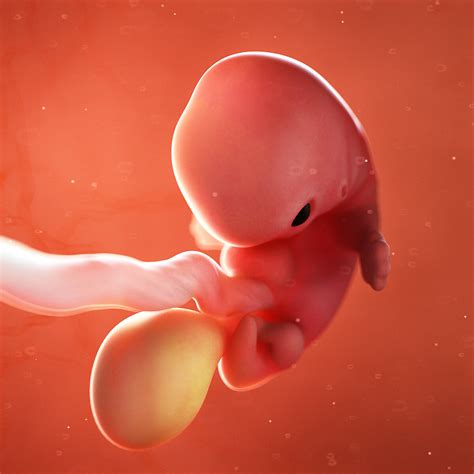

• week 7 pregnancy timeline

• pregnancy at week 7